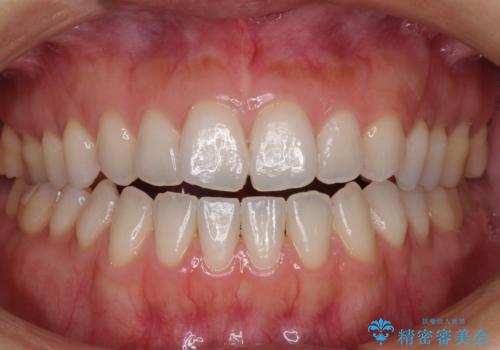

[ 前歯開咬 ] 前歯が噛んでいない マウスピース矯正治療

担当医 大元洋佑

![[ 前歯開咬 ] 前歯が噛んでいない マウスピース矯正治療の症例 治療後](https://seimitsushinbi.jp/wp/wp-content/uploads/2022/11/IMG_2488-500x350.jpg?v=1668218373)